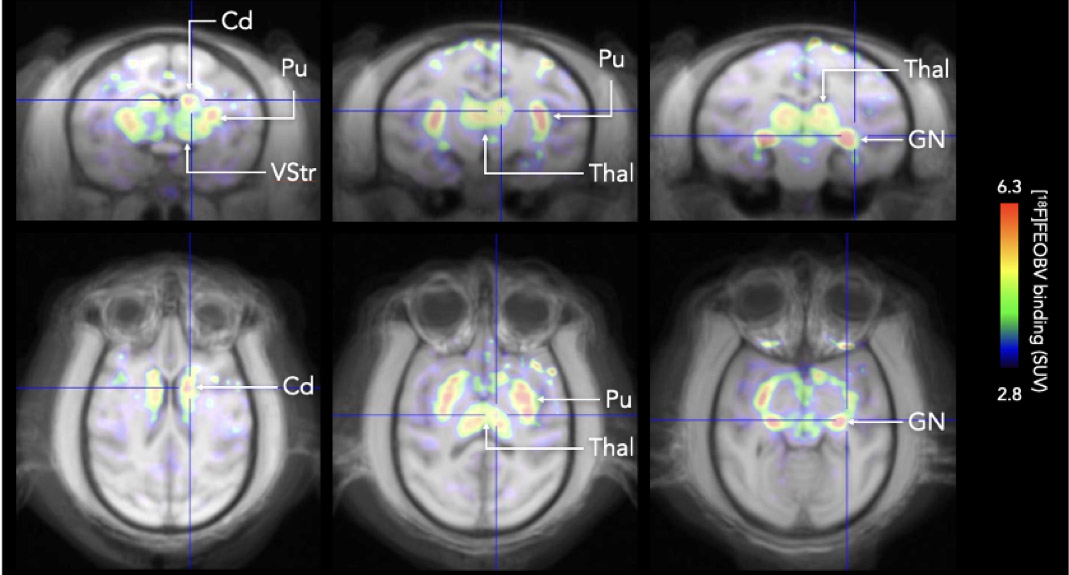

CASE 2: NHP brain PET imaging with [18F]FEOBV

• Courtesy of: University of Tours, Preclinical imaging department - PST ASB

Research objective: Study of [18F]FEOBV uptake in NHP brain

Animal model: Female Macaca fascicularis, 2.9 kg

Acquisition protocol: PET dynamic acquisition for 121 min, starting 1 min before injection

Processing and reconstruction protocol: Image reconstruction with following frames: 1x60s, 18x30s, 11x60s, 10x10min, 3D OSEM, 0.84 mm isotropic voxel size

Biomarker or contrast agent: [18F]FEOBV, 92 MBq

Image analysis: Software: PMOD v4.2. Image co-registered on a brain Macaca fascicularis MRI template (www.cermep.fr/download/atlas)